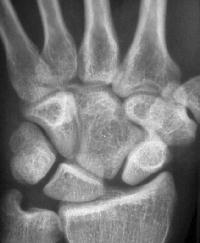

The opposite wrist is similar. This anatomy probably represents congenital carpal coalition between the capitate and an os centrale.